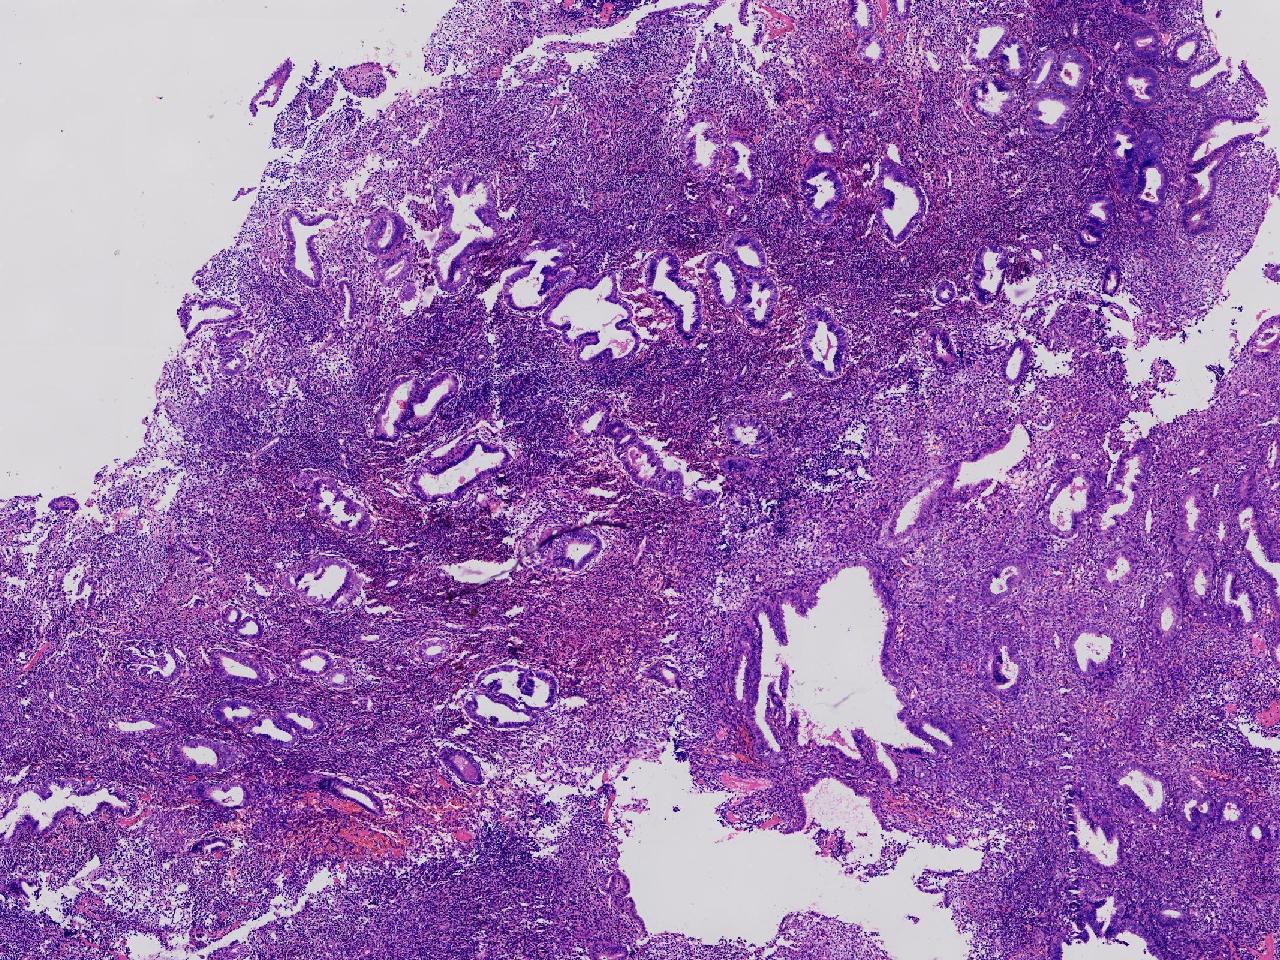

请教诊断。局灶够不够非典?

阴道不规则出血20余日,彩超示:内膜线居中,厚15毫米。

子宫内膜

灰粉色不整形软组织多块,3X2X1厘米。

不够非典

有输卵管上皮化生,感觉不够非典。